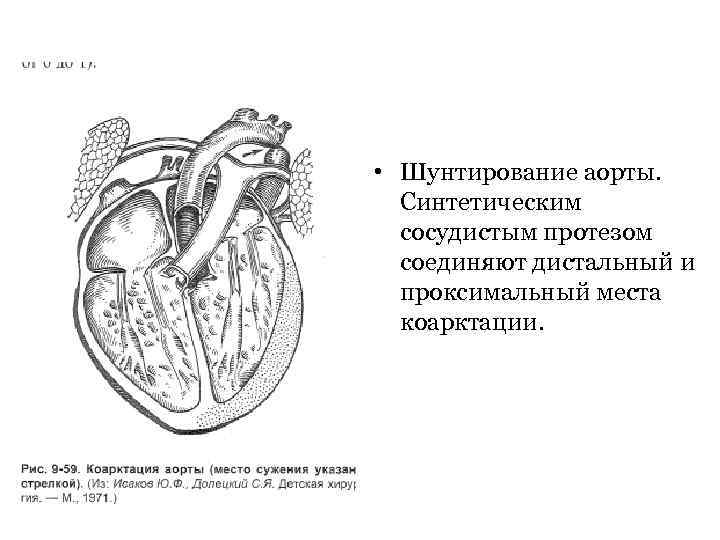

• Шунтирование аорты. Синтетическим сосудистым протезом соединяют дистальный и проксимальный места коарктации.

• Шунтирование аорты. Синтетическим сосудистым протезом соединяют дистальный и проксимальный места коарктации.